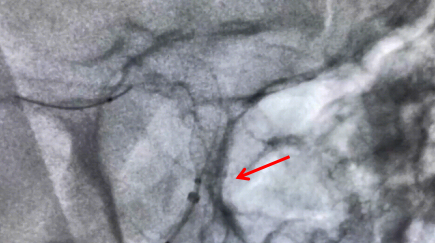

手术中释放支架图片

牟科杰主任医师介绍,颅内动脉瘤是血管壁形成的囊状突起,是颅内“不定时炸弹”,动脉瘤介入治疗,已经从弹簧圈栓塞时代进展到了血流导向密网支架治疗的时代。传统的治疗方法是单纯弹簧圈栓塞或支架辅助弹簧圈栓塞或开颅夹闭,但对于一些瘤颈宽、瘤体大、多发动脉瘤的患者,血流导向装置成为一种最佳的治疗手段。通过血流导向密网支架的释放,重建血管内血流方向,使动脉瘤血栓化,促进血管内皮的再生及修复,最终使瘤颈闭合而治愈。血管重建技术是颅内动脉瘤血管内治疗的重大突破,它使得一些复杂的脑动脉瘤治疗风险相对降低,术后复发率低,同时也让手术时间大为缩短,为复杂动脉瘤的治疗带来了全新方法。4月19日上午,手术历时两小时顺利完成。